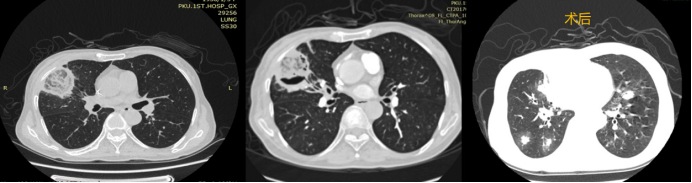

病例4:一例白血病合并毛霉感染患者。影像学检查可见胸膜下反晕征及空气新月征(图4)。该患者经内科治疗病情好转后,接受了手术切除治疗,但术后2周出现感染再次播散,最终不幸死亡。此病例表明,即使采用内科治疗联合手术切除的传统方案,肺毛霉病仍可能因感染播散导致不良结局。

图片

4  病例4手术前后胸部CT